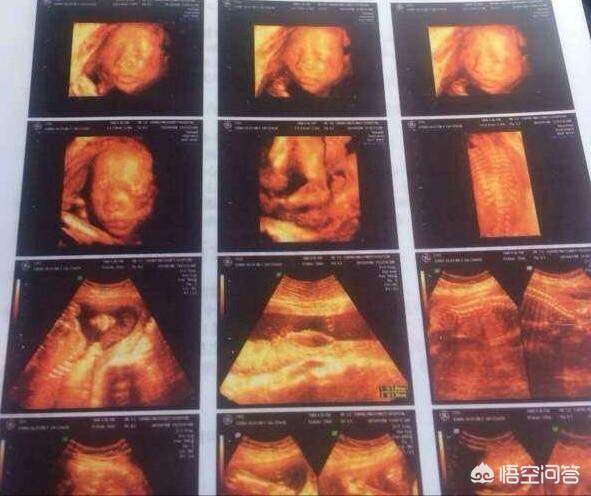

Lors d'une échographie 4D à huit mois, vous pouvez voir très clairement l'état du bébé, même les plus petites articulations comme les doigts et les orteils. Si le fœtus présente le moindre problème, l'échographiste est tenu de vous en informer. La phrase "les jambes du bébé sont longues" peut être une plaisanterie, le médecin ne vous dira pas le problème sur le ton de la plaisanterie, mais il vous dira directement s'il y a un problème réel.